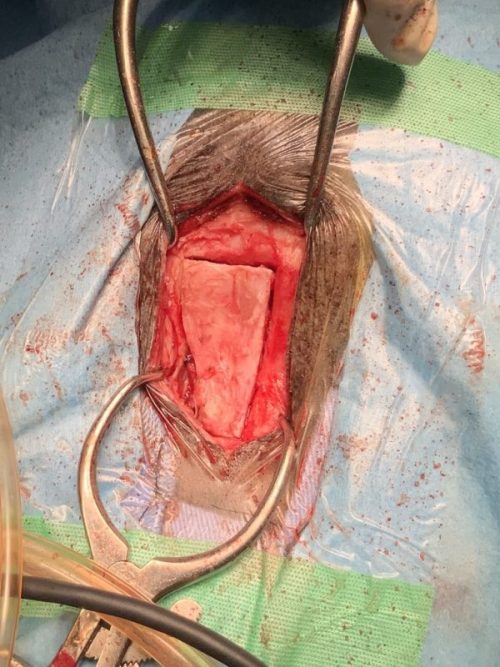

再手術

2025年12月15日(土)

手術は15時すぎから1時間半ほどでおわったようです。